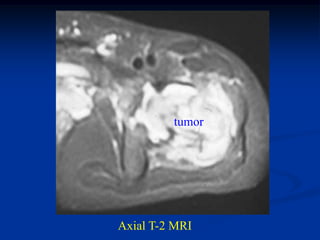

Axial T-2 MRI

Tumor seen thru cortical window